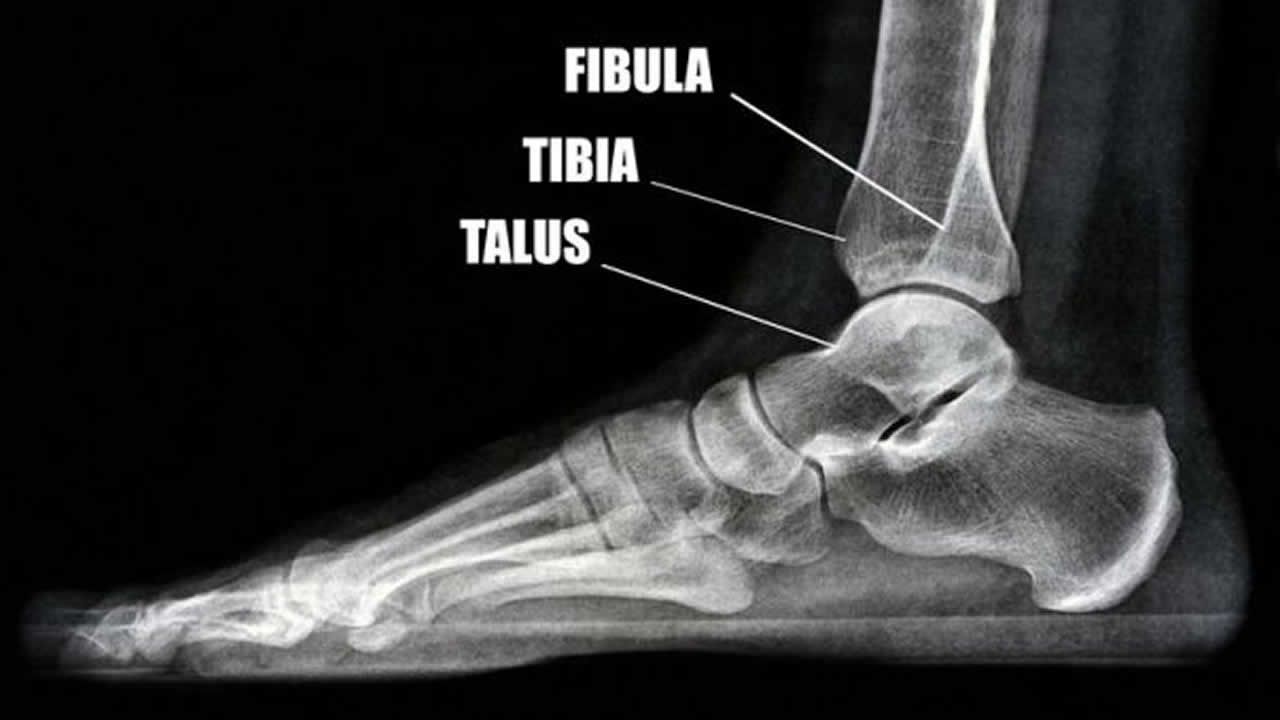

Yasmine M. a eu le tibia du pied gauche écrasé lors d’un accident de la route, le 30 janvier dernier, sur la route Royale, à Saint-Pierre (vis-à-vis de la gare). Elle est descendue de la voiture conduite par son mari et à peine avait-elle posé les pieds sur le trottoir quand un véhicule, sous l’impact d’une collision avec un autre véhicule, est venue la heurter de plein fouet.

Transportée à l’hôpital Dr A. G. Jeetoo, la femme y a passé 14 jours. Une vis a été posée à l’intérieur de son pied mais elle a fini par causer une infection. Imteeaz avance que le médecin de l’hôpital a refusé d’admettre que c’est le métal qui causait l’infection, ce qui l’a forcé de sortir son épouse de l’hôpital pour la faire admettre dans une clinique privée. Là-bas, on a enlevé la vis de son pied pour lui poser une structure métallique à l’extérieur.